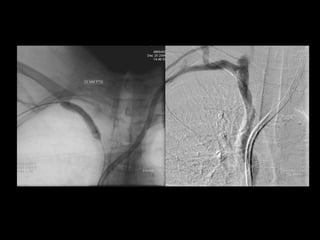

Effort Thrombosis:

36 YO weightlifter

Post-Op 1st rib resection